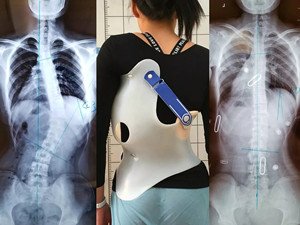

在青少年快速發(fā)育期內(nèi),身體長(zhǎng)得越快,脊柱側(cè)彎的進(jìn)展就越快。矯形支具通過長(zhǎng)時(shí)的反向矯正力將脊柱維持在一個(gè)矯正的狀態(tài);然而由于長(zhǎng)時(shí)間地佩戴支具會(huì)導(dǎo)致肌肉萎縮,當(dāng)支具摘除,脊柱側(cè)彎回彈,且患者無法形成成自我矯正力,呼吸功能亦無法得到改善。最好是在穿戴支具的同時(shí),配合體操訓(xùn)練,通過一系列矯正動(dòng)作以及呼吸訓(xùn)練,平衡肌力,兩者結(jié)合不但可以穩(wěn)定脊柱,且能增加改善機(jī)會(huì)。